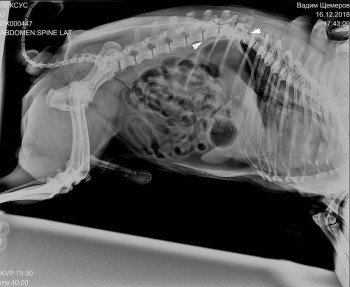

Здравствуйте. Собаке (мопс, 13 лет) поставили диагноз:

спондилолистез и спондилоартроз. Смещение позвонков и грыжа, от чего собака имеет шатающуюся походку, хвостик чаще опушен. Прописали препапараты. Почитала и ужаснулась. Как помочь моему любимцу? Спасибо.

Мопс 13 лет, грыжа и шатающяяся походка